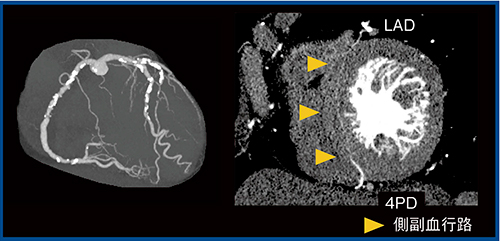

当センターではFIRSTを積極的に使用したいと考えているが,冠動脈CTにおいては制限がある。FIRSTは現状ではハーフ再構成のみの対応のため,Aquilion Precisionで撮影する症例は,低心拍(HR 60以下),BMI 26以下を参考にしている。不整脈症例や息止めができない小児症例では,ADCTの方が良好な画像を得られるため,臨床目的に合わせた装置の使い分けが大切である。Aquilion Precisionでは,左前下行枝(LAD)から右後下行枝(4PD)への中隔を貫く側副血行路の描出なども可能であった(図9)。高い空間分解能が生かされる領域を見極めて活用することが重要である。

図9 LADから4PDへの側副血行路の描出